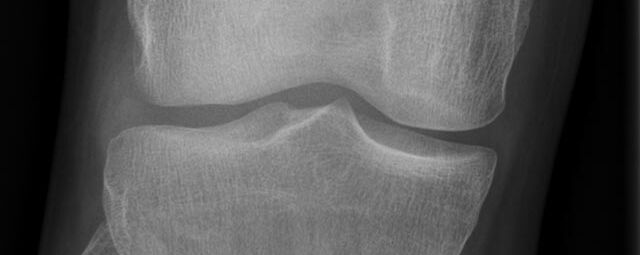

Röntgen Knochen

• Fraktur

• Arthrose

• Rheumatische Gelenkerkrankungen

• Degenerative Veränderungen der Wirbelsäule

• Knochentumor

• Osteoporose

• Therapiekontrolle nach OP am Skelettsystem